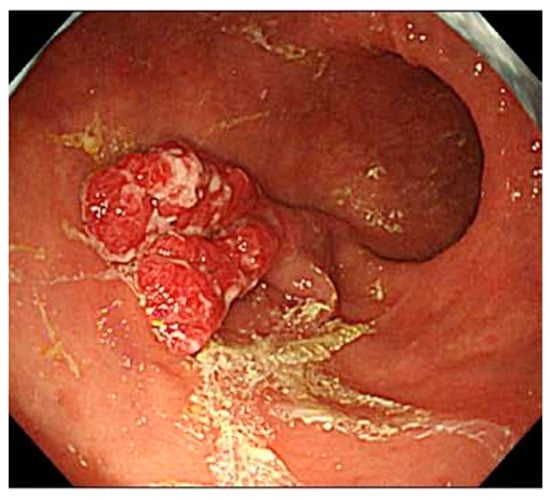

- Kotera, T.; Oe, K.; Kushima, R.; Haruma, K. Multiple Pseudopolyps Presenting as Reddish Nodules Are a Characteristic Endoscopic Finding in Patients with Early-stage Autoimmune Gastritis. Intern. Med. 2020, 59, 2995–3000. [Google Scholar] [CrossRef]